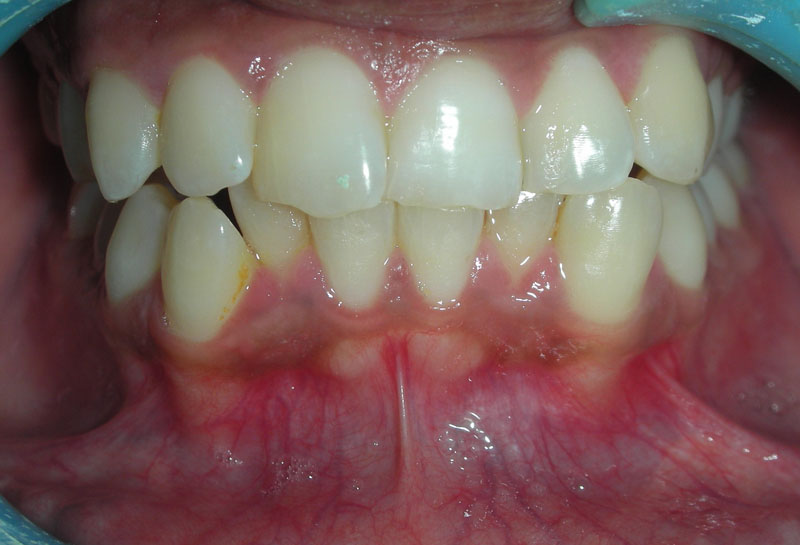

After